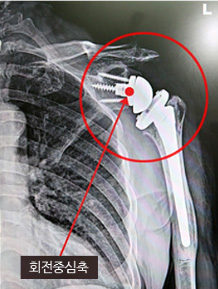

| 구분 | 기존 어깨인공관절수술 | 역방향 어깨인공관절수술 |

|---|---|---|

| 사진 | ![]() |

![]() |

| 대상 |

- 60대 이상 고령층 - 퇴행성관절염, 외상으로 관절기능이 손상된 자 |

- 65대 이상 고령층 - 회전근개 파열로 봉합이 불가능하고 가성마비가 있는 경우. 단, 삼각근은 정상이어야 함 |

| 방법 |

- 65세 이상 고령층 - 본래 골격 모양과 유사한 인공관절 사용 - 뼈를 인공관절로 교체, 힘줄은 봉합 안함 |

- 본래 골격과 반대되는 모양의 인공관절 사용 - 파열된 회전근개 대신 삼각근 이용 |

| 특징 |

- 회전 중심축이 어깨 바깥쪽에 위치 |

- 회전중심축이 어깨 안쪽에 위치 |

| 단점 |

- 통증은 회복되지만 가성마비가 있는 경우 마비 증세는 회복 안됨 |

- 인공관절 각도에 따라 팔 드는 각도 달라져 수술 난이도 높음 |